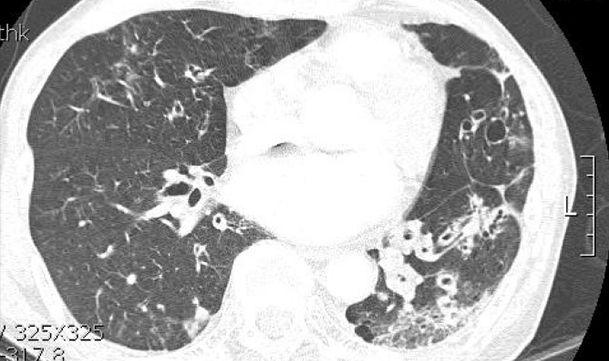

환자의 임상 증상 문진과 진찰 후, 흉부 X선 검사 및 흉부 CT가 진단에 도움이 됩니다.

• 폐결핵 비결핵성항상균 폐질환

img img

그림: 폐결핵과 비결핵성항산균 폐질환의 흉부엑스레이 사진과 흉부전산화단층활영 사진

비결핵성항산균 폐질환은 폐결핵과 비교하였을 때 서서히 진행하거나 변하지 않을 수 있으며, 만성적인 경과를 보이고, 진단이 늦어지는 경향이 있습니다. 두 질환은 모두 환자의 객담을 통한 객담 항산균 도말검사, 객담 항산균 배양 검사를 진행합니다. 객담 배양이 되기 전에는 객담 도말 검사 양성 소견만으로는 결핵균과 비결핵성항산균이 구별이 되지 않으며, 구별을 위해서 결핵균 핵산증폭검사(TB-PCR) 검사를 시행합니다.